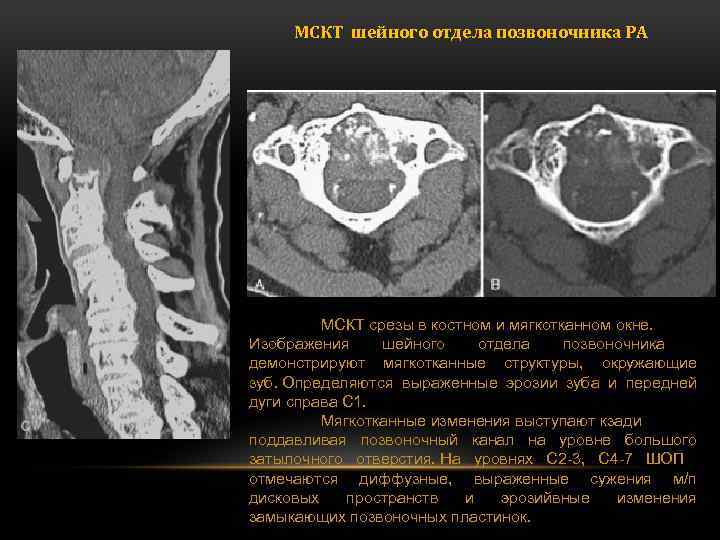

МСКТ шейного отдела позвоночника РА МСКТ срезы в костном и мягкотканном окне. Изображения шейного отдела позвоночника демонстрируют мягкотканные структуры, окружающие зуб. Определяются выраженные эрозии зуба и передней дуги справа C 1. Мягкотканные изменения выступают кзади поддавливая позвоночный канал на уровне большого затылочного отверстия. На уровнях С 2 -3, С 4 -7 ШОП отмечаются диффузные, выраженные сужения м/п дисковых пространств и эрозийвные изменения замыкающих позвоночных пластинок.